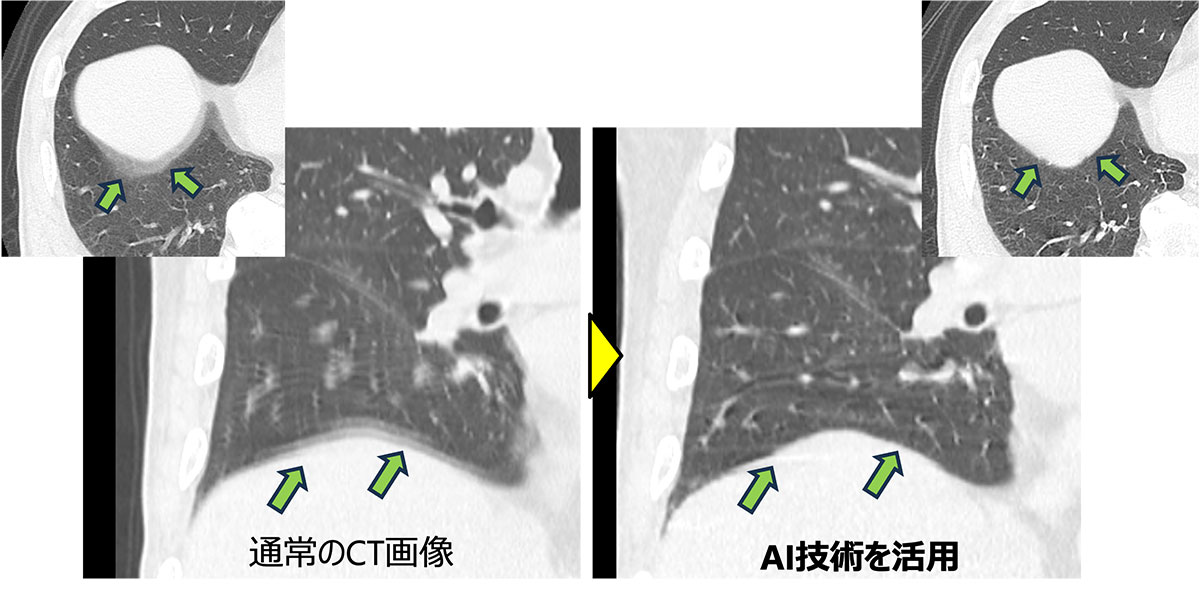

人工知能(AI)技術と特殊機能

新たなAI技術と特殊機能が多く備わりました。すべてのCT検査に対してAI技術を活用してCT画像の大幅な画質の向上につなげています。さらに画像が劣化する原因となるもの(金属・動き)に対して特殊機能を活用することで、結果の精度と信頼性の向上が期待できます。

肺のCT画像。呼吸を止められず動いてしまった画像(左)に対して、AI技術を活用し呼吸が止まった状態で画像を提供できた(右)。